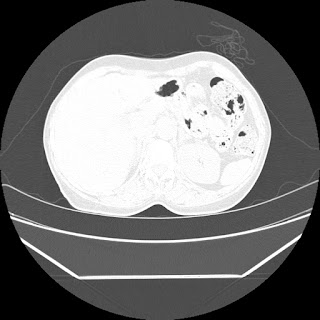

HRCT is also done on 13/11/15